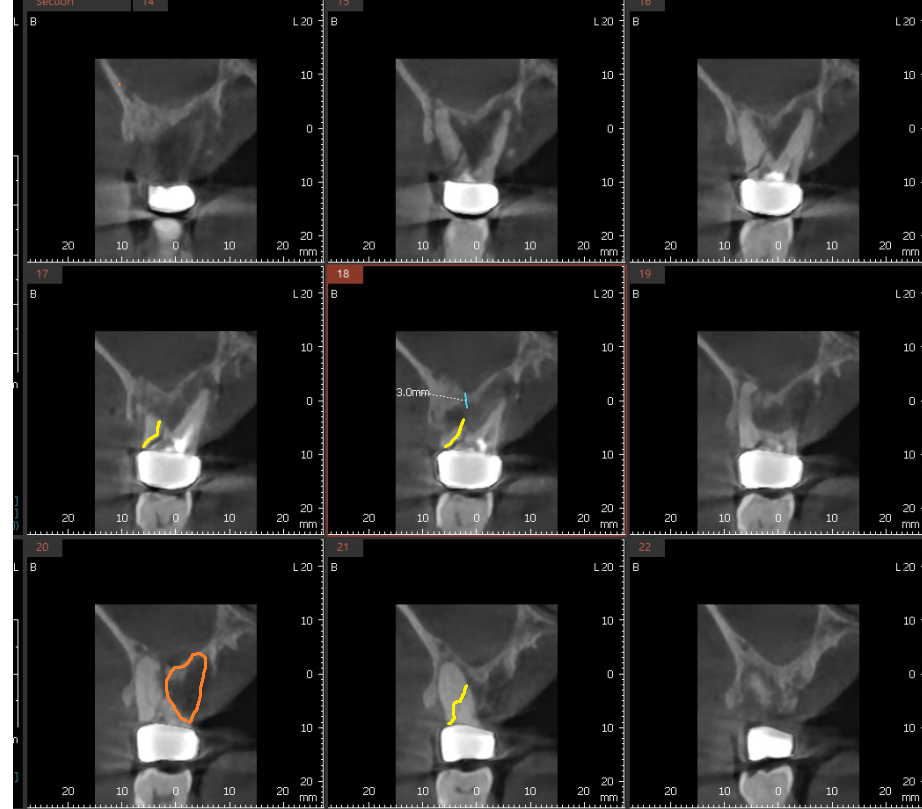

ct를 촬영해보니 한쪽 뿌리가 팔 뿌러지듯

골절 선이 보입니다.

치아 뿌리가 파절되면서 염증이 생기고

주변 잇몸뼈를 녹였습니다.

3개월 뒤 망월동 치과 재방문하여 찍어본 x ray

어느정도 잇몸뼈가 만들어지긴 하였지만

2.3mm의 길이만 확보되었습니다.

최소 6mm가 더 필요하여

2차 뼈이식을 진행하면서 임플란트를 심었습니다.